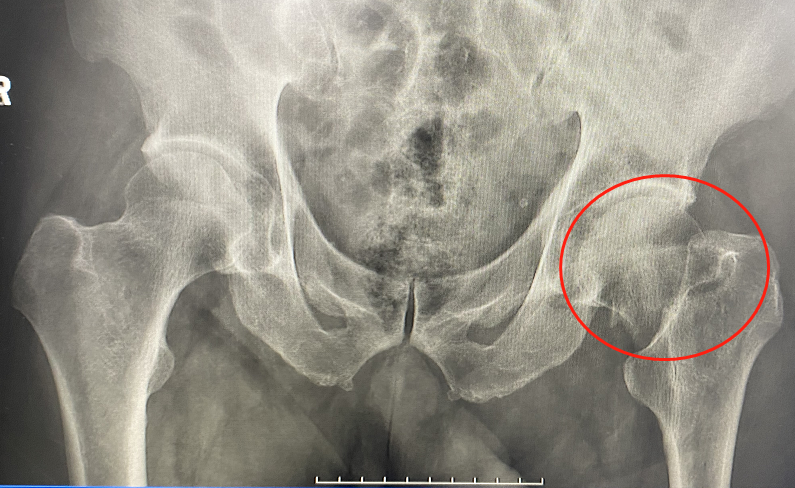

不久前,85岁的陈大爷跌倒了,左髋疼痛,不能坐立,只能平躺,左下肢不能活动。拍片结果显示为 “左侧股骨颈骨折”。这可愁坏了陈大爷的几个儿女,骨科徐光辉副主任医师在对老人家的心肺功能,一般情况做过评估后,建议骨科微创手术,避免产生因骨折卧床的长期并发症,又能让老人家早日恢复,最大程度保证老人骨折前的生活质量。

▲手术前左侧股骨颈骨折